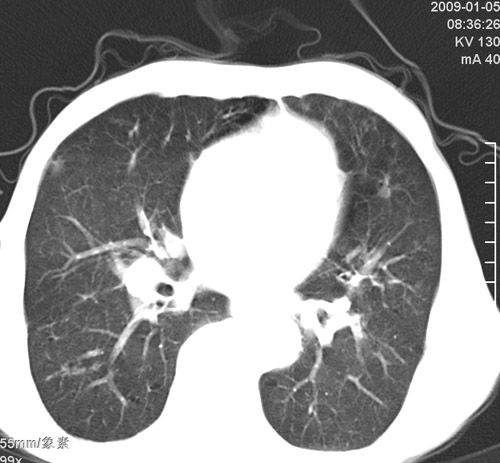

标题: CT17529:男 76 胸背部不适半月 胸透支气管炎 行CT检查 [打印本页]

标题: CT17529:男 76 胸背部不适半月 胸透支气管炎 行CT检查

意见 老年肺 少许炎症 肺大泡 右肺门略大 但支气管通畅  请各位高手指教如何下意见

间质纤维化伴少许炎症!另:肺大泡形成!

支持楼主意见,右肺门略大,可能为肺动脉增粗.

慢支肺气肿,肺动脉高压.